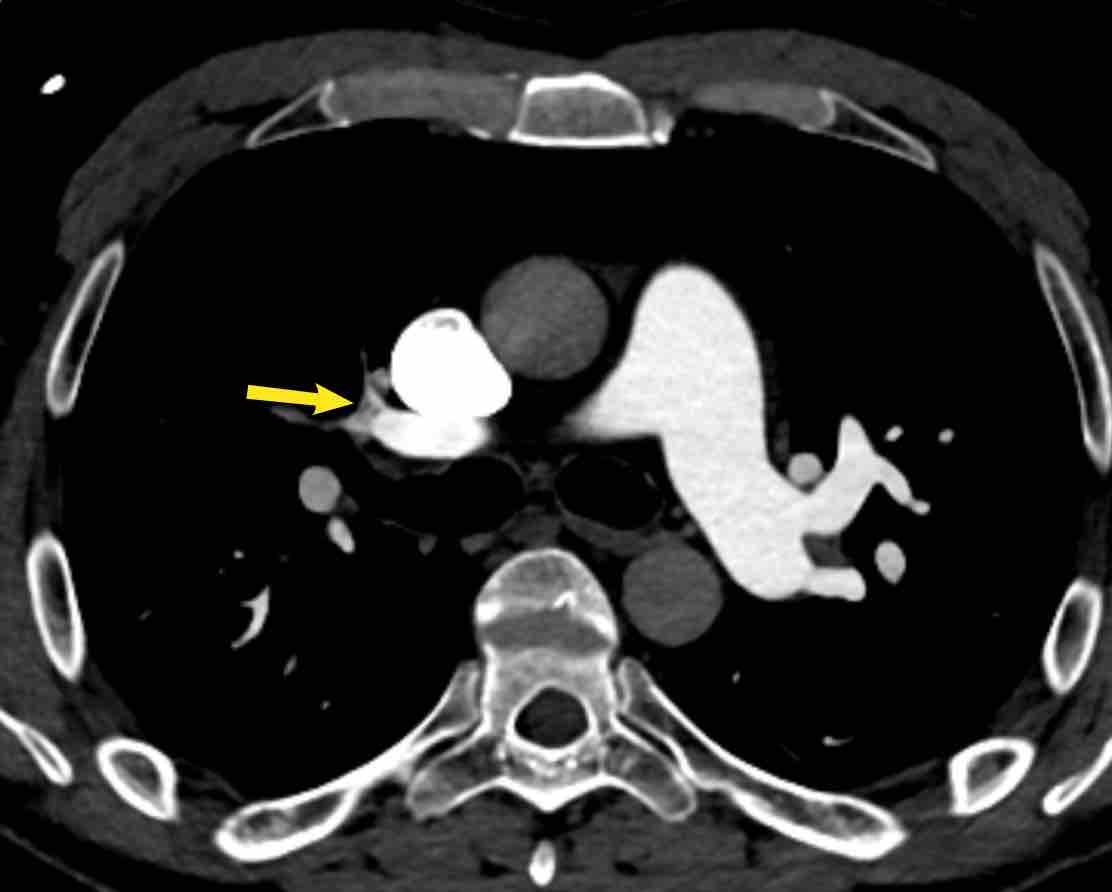

Hình ảnh

- Màng ngăn (web) phân thùy hai bên (mũi tên đen)

- Màng ngăn phân thùy kèm hẹp đột ngột động mạch dưới phân thùy ở phía xa (mũi tên vàng).

- Hình ảnh MIP cho thấy màng ngăn phân thùy hai bên kèm hẹp đột ngột động mạch dưới phân thùy ở phía xa (đầu mũi tên)

Kết luận

Màng ngăn phân thùy hai bên, kèm hẹp đột ngột động mạch dưới phân thùy ở phía xa,

phù hợp với tăng áp động mạch phổi do huyết khối tắc mạch mạn tính (CTEPH).